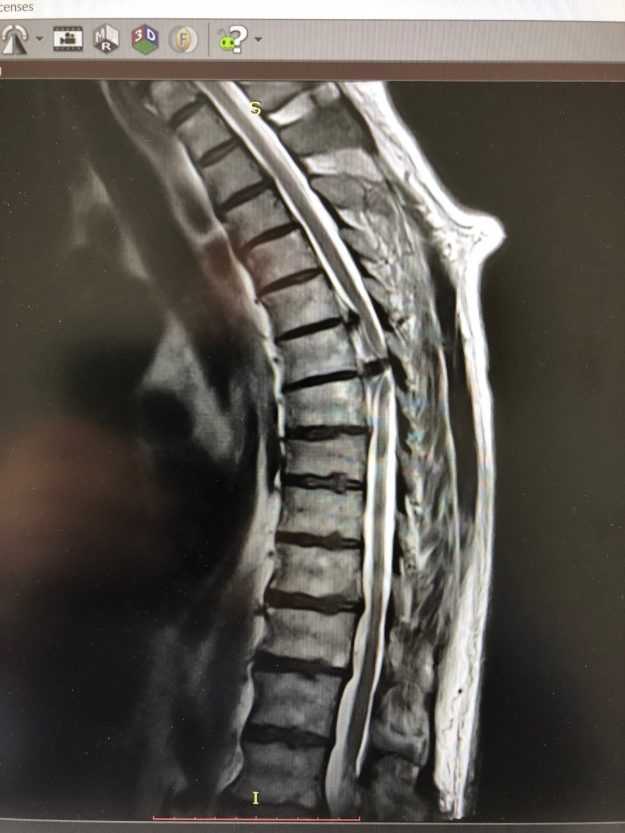

Μετάσταση 10ου Θωρακικού Σπονδύλου (Θ10)

Ασθενής άνδρας 72 ετών με έντονη ραχιαλγία και ιστορικό καρκίνου του πνεύμονα. Ο απεικονιστικός έλεγχος με μαγνητική και αξονική τομογραφία της σπονδυλικής στήλης ανέδειξε μάζα κυρίως στο σώμα του 10ου θωρακικού σπονδύλου (Θ10) με περιβρογχισμό και πίεση επί του νωτιαίου μυελού. (Σημειώστε και τη διήθηση του Θ9 σπονδύλου, χωρίς οστεόλυση). Διενεργήθη αποσυμπίεση του νωτιαίου μυελού…